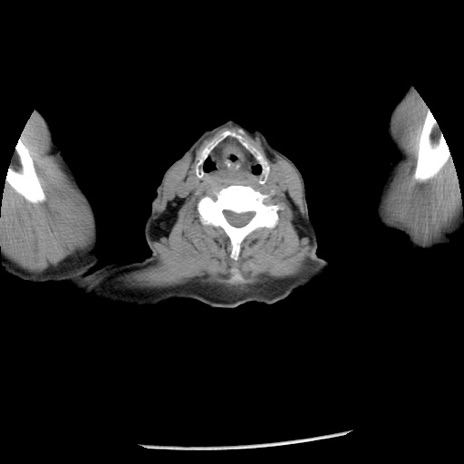

冠状断像